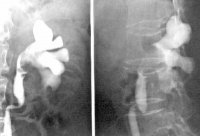

本病诊断方法基本同肾癌,大量反复肉眼血尿,血尿严重时可见输尿管管型血块。查体常无阳性体征发现,血尿发作时膀胱镜检查可见患侧输尿管口喷血,尿液细胞学检查可见肿瘤细胞。B超、CT检查可见肾盂实质占位性病变,静脉肾盂造影或逆行肾盂造影可见肾盂或肾盏内有不规则的充盈缺损。尿细胞学检查可查见癌细胞。